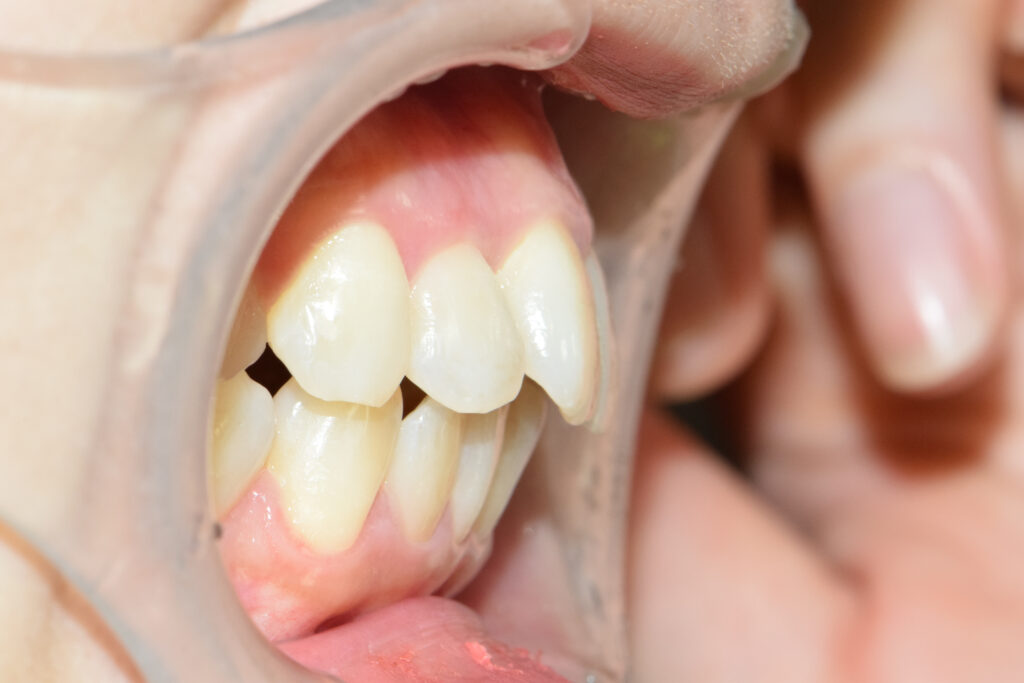

オーバージェット

治療後